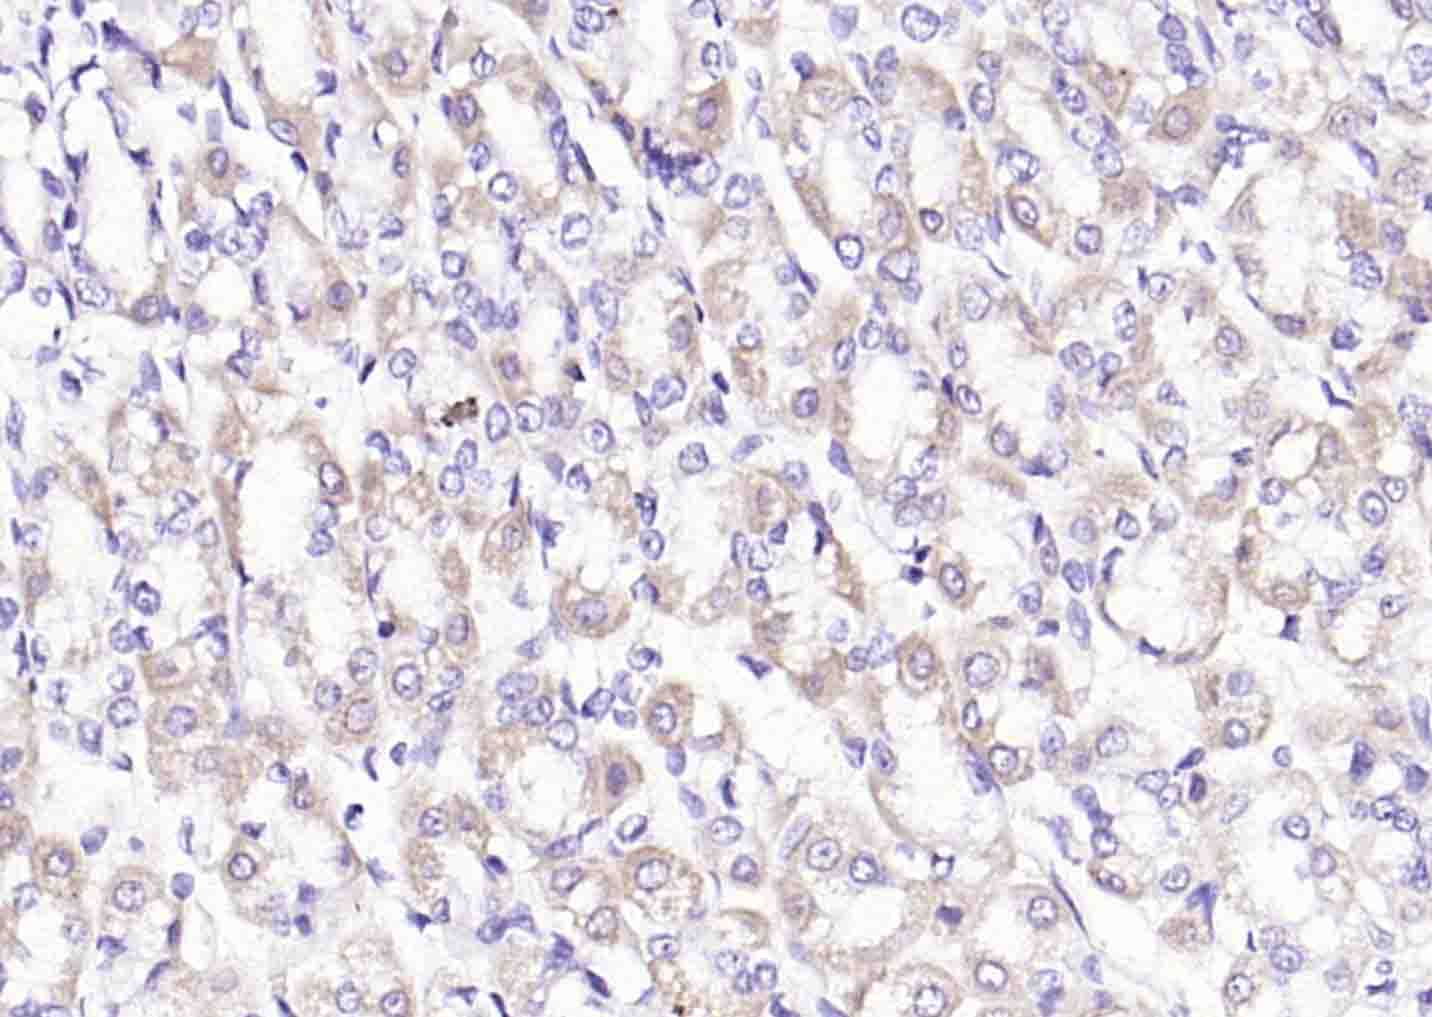

Paraformaldehyde-fixed, paraffin embedded (human lung carcinoma); Antigen retrieval by boiling in sodium citrate buffer (pH6.0) for 15min; Block endogenous peroxidase by 3% hydrogen peroxide for 20 minutes; Blocking buffer (normal goat serum) at 37°C for 30min; Incubation with (PDHA1) Polyclonal Antibody, Unconjugated (bs-4034R) at 1:200 overnight at 4°C, followed by operating according to SP Kit(Rabbit) (sp-0023) instructionsand DAB staining.

Paraformaldehyde-fixed, paraffin embedded (human stomach); Antigen retrieval by boiling in sodium citrate buffer (pH6.0) for 15min; Block endogenous peroxidase by 3% hydrogen peroxide for 20 minutes; Blocking buffer (normal goat serum) at 37°C for 30min; Incubation with (PDHA1) Polyclonal Antibody, Unconjugated (bs-4034R) at 1:200 overnight at 4°C, followed by operating according to SP Kit(Rabbit) (sp-0023) instructionsand DAB staining.

Paraformaldehyde-fixed, paraffin embedded (rat stomach); Antigen retrieval by boiling in sodium citrate buffer (pH6.0) for 15min; Block endogenous peroxidase by 3% hydrogen peroxide for 20 minutes; Blocking buffer (normal goat serum) at 37°C for 30min; Incubation with (PDHA1) Polyclonal Antibody, Unconjugated (bs-4034R) at 1:200 overnight at 4°C, followed by operating according to SP Kit(Rabbit) (sp-0023) instructionsand DAB staining.

Paraformaldehyde-fixed, paraffin embedded (Rat heart); Antigen retrieval by boiling in sodium citrate buffer (pH6.0) for 15min; Block endogenous peroxidase by 3% hydrogen peroxide for 20 minutes; Blocking buffer (normal goat serum) at 37°C for 30min; Antibody incubation with (PDHA1) Polyclonal Antibody, Unconjugated (bs-4034R) at 1:400 overnight at 4°C, followed by a conjugated secondary antibody (sp-0023) for 20 minutes and DAB staining.